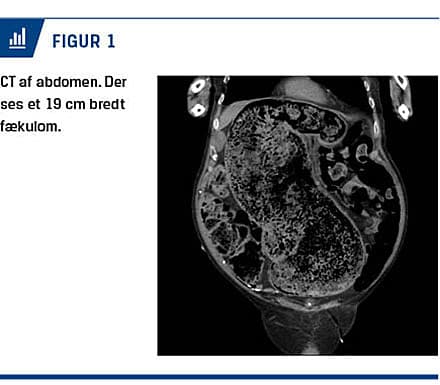

Ved en objektiv undersøgelse fandt man et spændt abdomen, hvorfor der blev foretaget CT af abdomen, hvorved man så en svært dilateret colon med en diameter på op til 19 cm pga. fækalier, men ingen tegn til mekanisk obstruktion eller perforation (Figur 1).